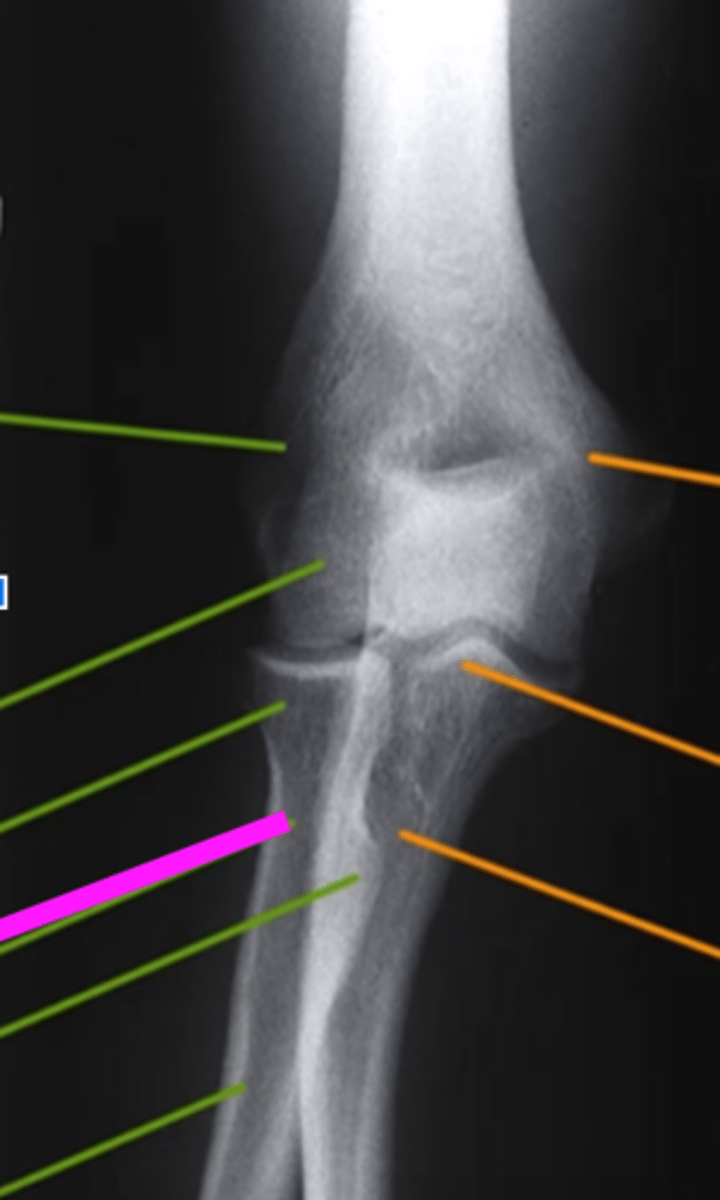

AP Elbow

what view is this

lateral epicondyle

what does the pink line point to?

medial epicondyle

Capitulum

coronoid process

shaft of ulna

shaft of the radius

radial tuberosity

radial head

radial neck